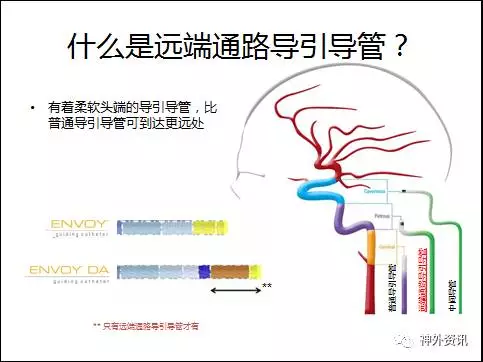

众所周知,传统的Envoy支撑性好,到位较低,满足大部分颅内血管的临床需要,对于血管严重迂曲和复杂动脉瘤的治疗需要导管提供更高的支撑力和更好地顺应性,所以有着更柔软头端,比普通导引导管上的更远的远端通路导引导管更能满足临床需求。

ENVOY® DA 远端通路导引导管在介入手术中可以突破颈内动脉岩谷段到达更远端甚至更下一级血管,在一些复杂颅内动脉瘤、终末支血管供血的AVM以及病变近端通路迂曲的情况下为微导管及支架导管提供了稳定的支撑力,为介入手术的成功提供了保障。

1. Envoy DA远端通路导引导管,是强生公司在Envoy导引导管的基础上研发的产品,在保留Envoy近端支撑力的同时,柔软的8cm柔软段能很好的锚定在迂曲的颅内血管中。对于绝大部分的神经介入复杂治疗不需要使用长鞘,为手术提供了便利。